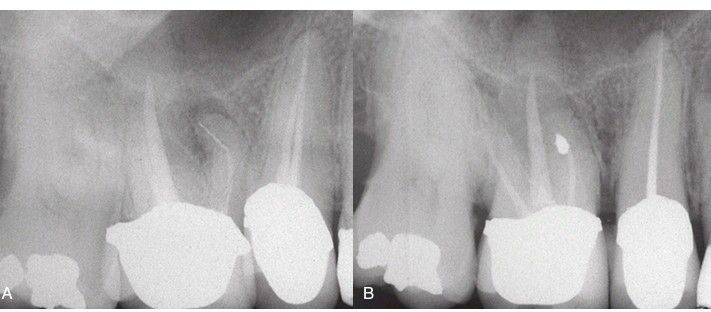

(A) Irretrievable material (arrow) in mesial and palatal canals and apical pathosis. (B) Canals are re-treated, but this has failed. (C) Treatment is root end resection to level of gutta-percha in the mesial and palatal aspects. (D) After 2 years, healing is complete.